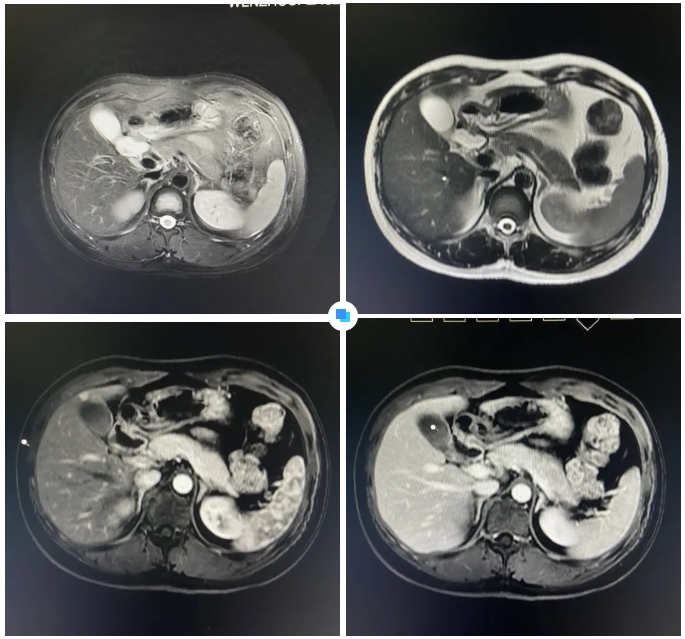

在被問到如何發(fā)現(xiàn)隱藏如此深的病灶時,和平國際醫(yī)院影像中心執(zhí)行主任侯文杰講到,該病灶在平掃T1、T2項都非常不清楚,只有彌散加權(quán)的情況下,病灶區(qū)域顯示出輕微的高信號,這一細微線索引起了他的高度關(guān)注。

隨后的增強核磁掃描發(fā)現(xiàn),在動脈期病灶顯著強化,而在門脈期明顯減退,這一特征與微小肝癌的表現(xiàn)高度吻合。